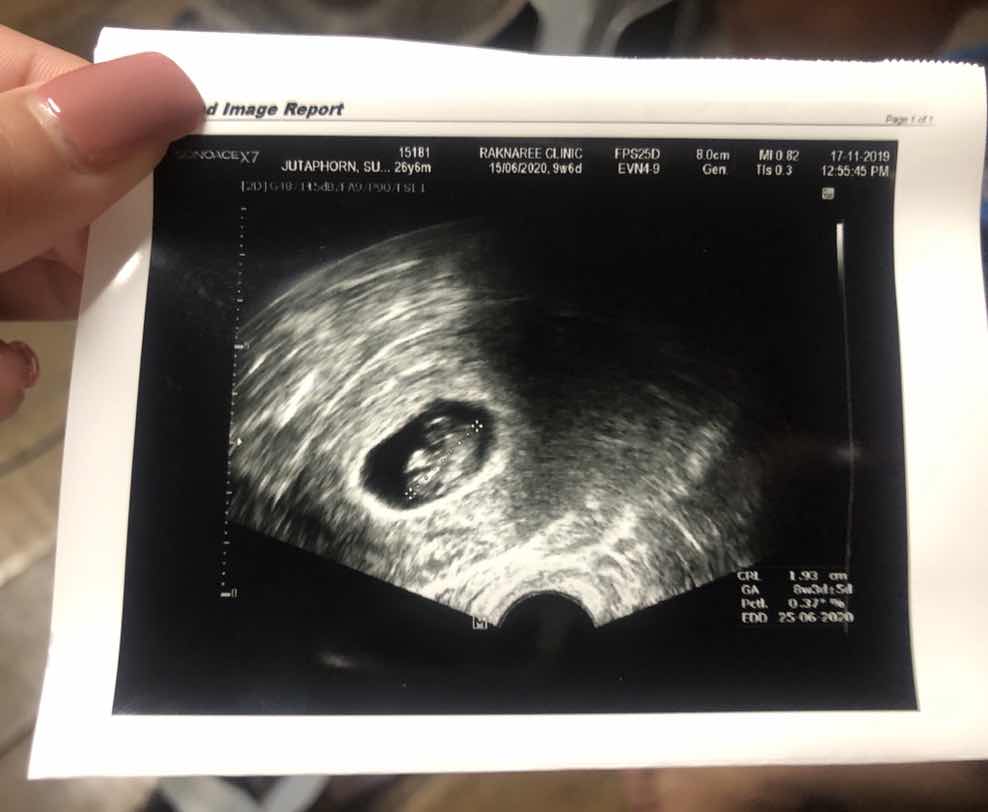

9 week 4day ค่ะ